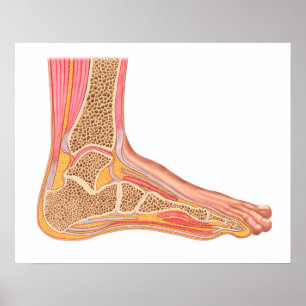

Poster Section Longitudinale Du Pied Humain

Prix37.05 CHF

Toile Section Longitudinale Du Pied Humain

Prix161.00 CHF